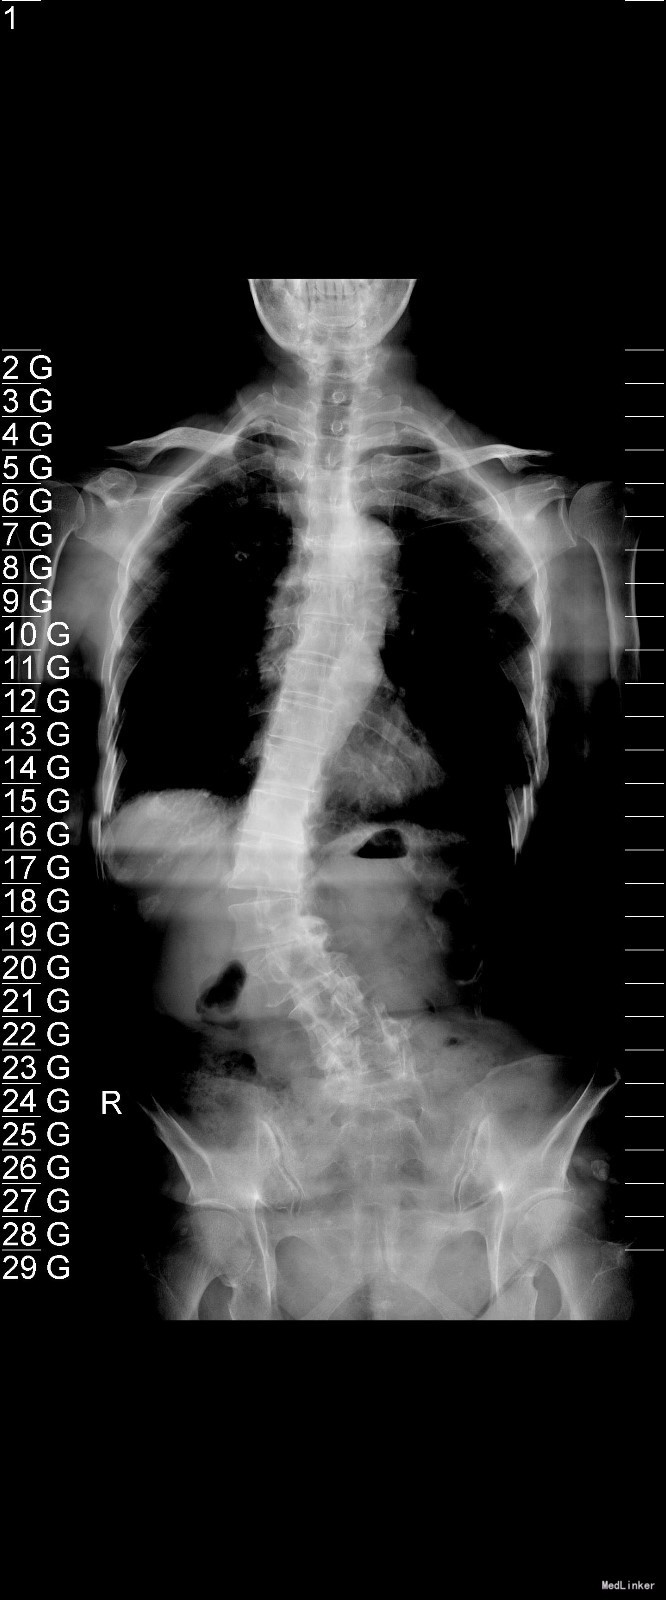

主诉:右下肢麻木11年,腰部酸痛无力 现病史:女性患者,65岁,患者于11年前无明显诱因下出现右下肢麻木,自大腿至右踝部,站立位加重。未予重视,后期出现腰臀部僵硬,弓背僵硬无力,自主行走距离不足200米,曾于06年经X线平片及MRI检查:腰椎椎管狭窄伴有腰椎滑脱,椎间盘突出等。

查体:侧弯畸形,右臀部及右下肢麻木疼痛,腰部活动受限,难以站立。右侧支腿抬高试验60°。双下肢肌力肌张力可。 辅助检查:平片:腰椎侧弯,椎体滑脱,曲度后凸 磁共振:L2-3,L4-5,L5-S1腰椎椎管狭窄,l2-3L3-4L4-5L5-S1腰椎间盘突出,腰椎退变

诊断: 腰椎侧弯,腰椎间盘突出 治疗:1期微创侧路椎体融合术+2期 微创后路经皮内固定术

随访:患者戴支具术后可早期下床活动,术后三周后行后路固定手术